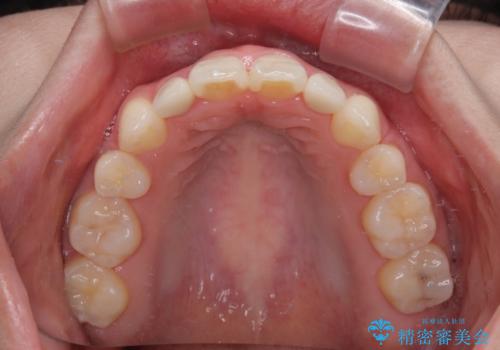

飛び出した前歯 インビザラインを用いた抜歯矯正治療

上下前歯同士の距離が離れているため、上顎左右第一小臼歯2本を抜歯することで前突を改善することとしました。

しかしながら、左右ともに側切歯が矮小歯であるため、矯正治療で矮小歯前後にスペースを作り、矯正治療後にオールセラミッククラウンにて補綴治療を行うこととしました。

治療途中で地元へ転居され、飛行機での通院となったため、治療期間が長くなりましたが、自然で整った口元に仕上げることができました。